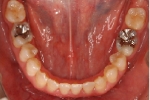

カテゴリー:開咬(overbiteがマイナスのもの)

| マルチブラケット終了時